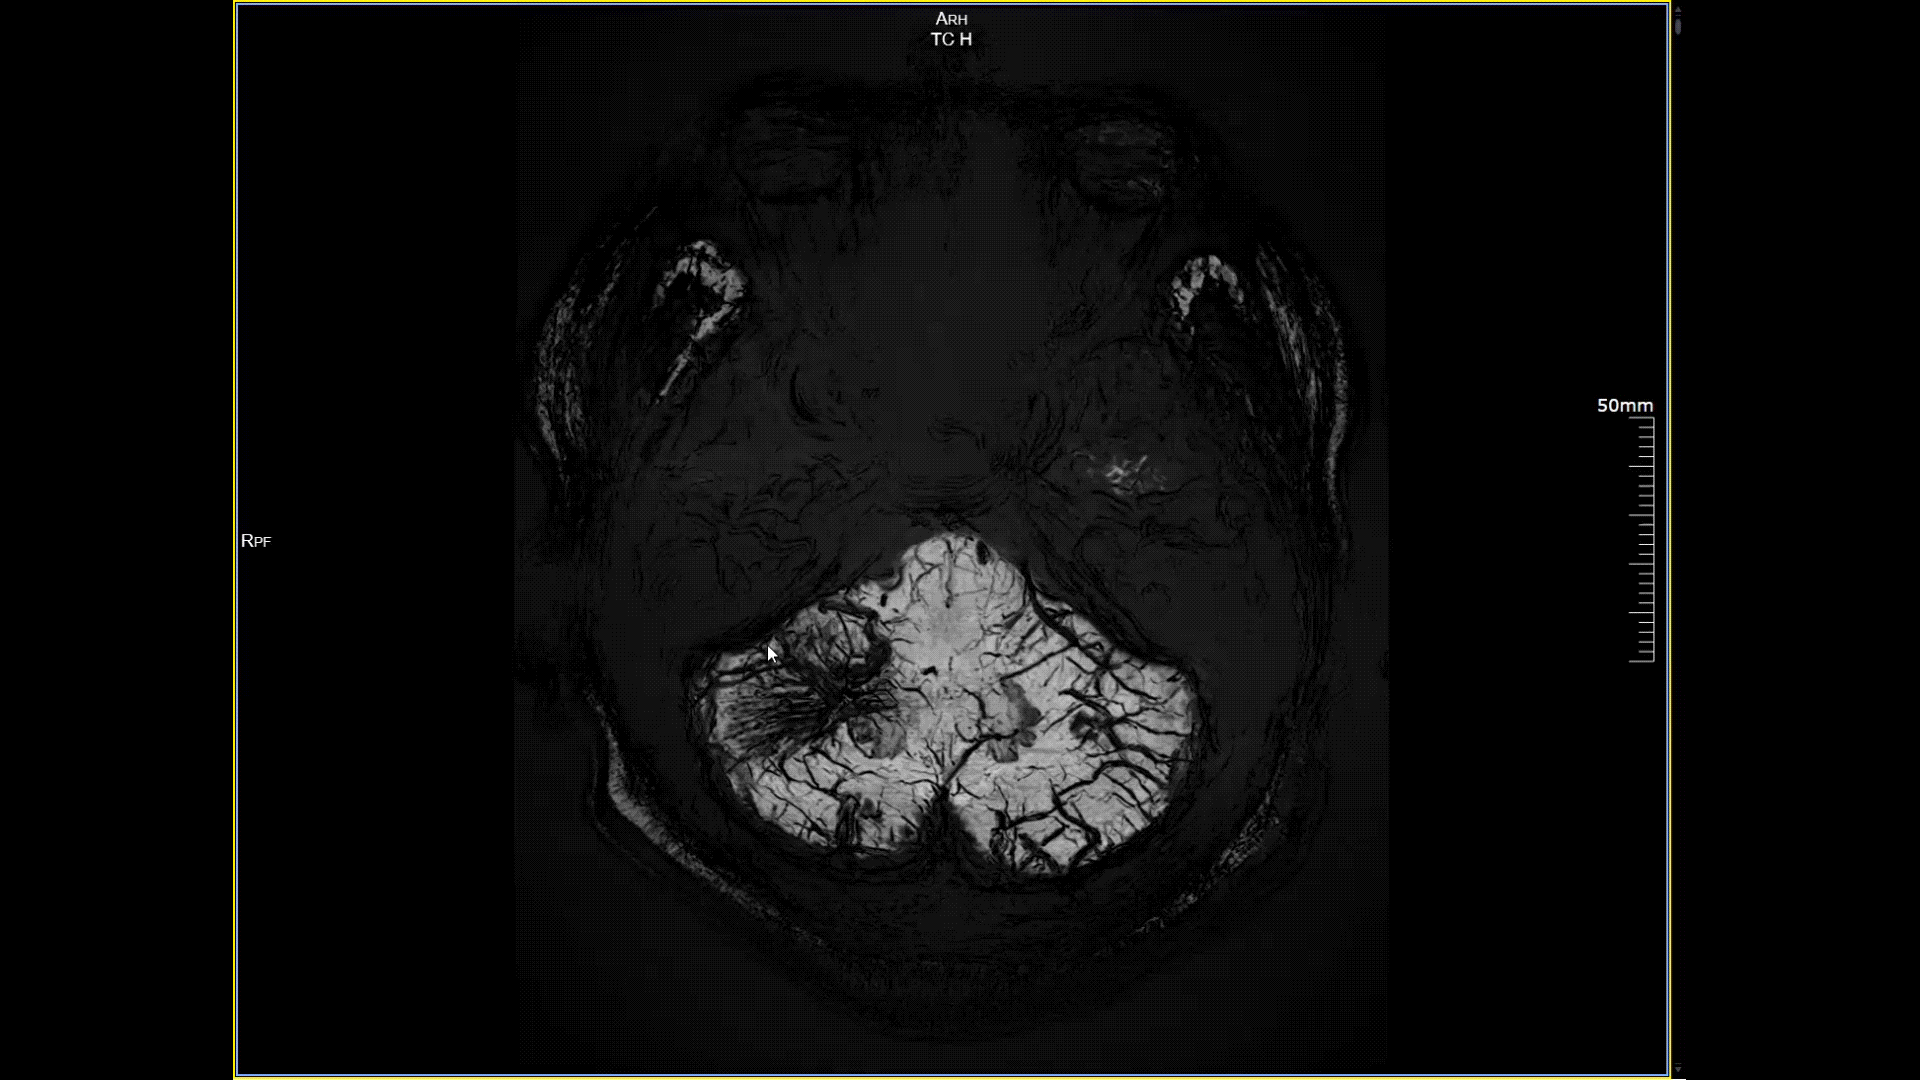

磁敏感成像SWI,分辨率0.2*0.2mm

5.0T磁场强度远高于其他设备,使得氢原子核在磁场中的响应信号极大地增强。这就像在安静的房间里能听清细微的声音一样,高信噪比能让医生看到更微小、更模糊的病变结构。例如上述患者的检查,该设备可以呈现0.2x0.2毫米高分辨率的图像以及动态显示血管走行,使得病变血管的细微解剖结构、分布及其与周边脑组织的关系得以直观呈现,为临床医生进行精准诊断并制定后续治疗方案提供了重要的影像学依据。